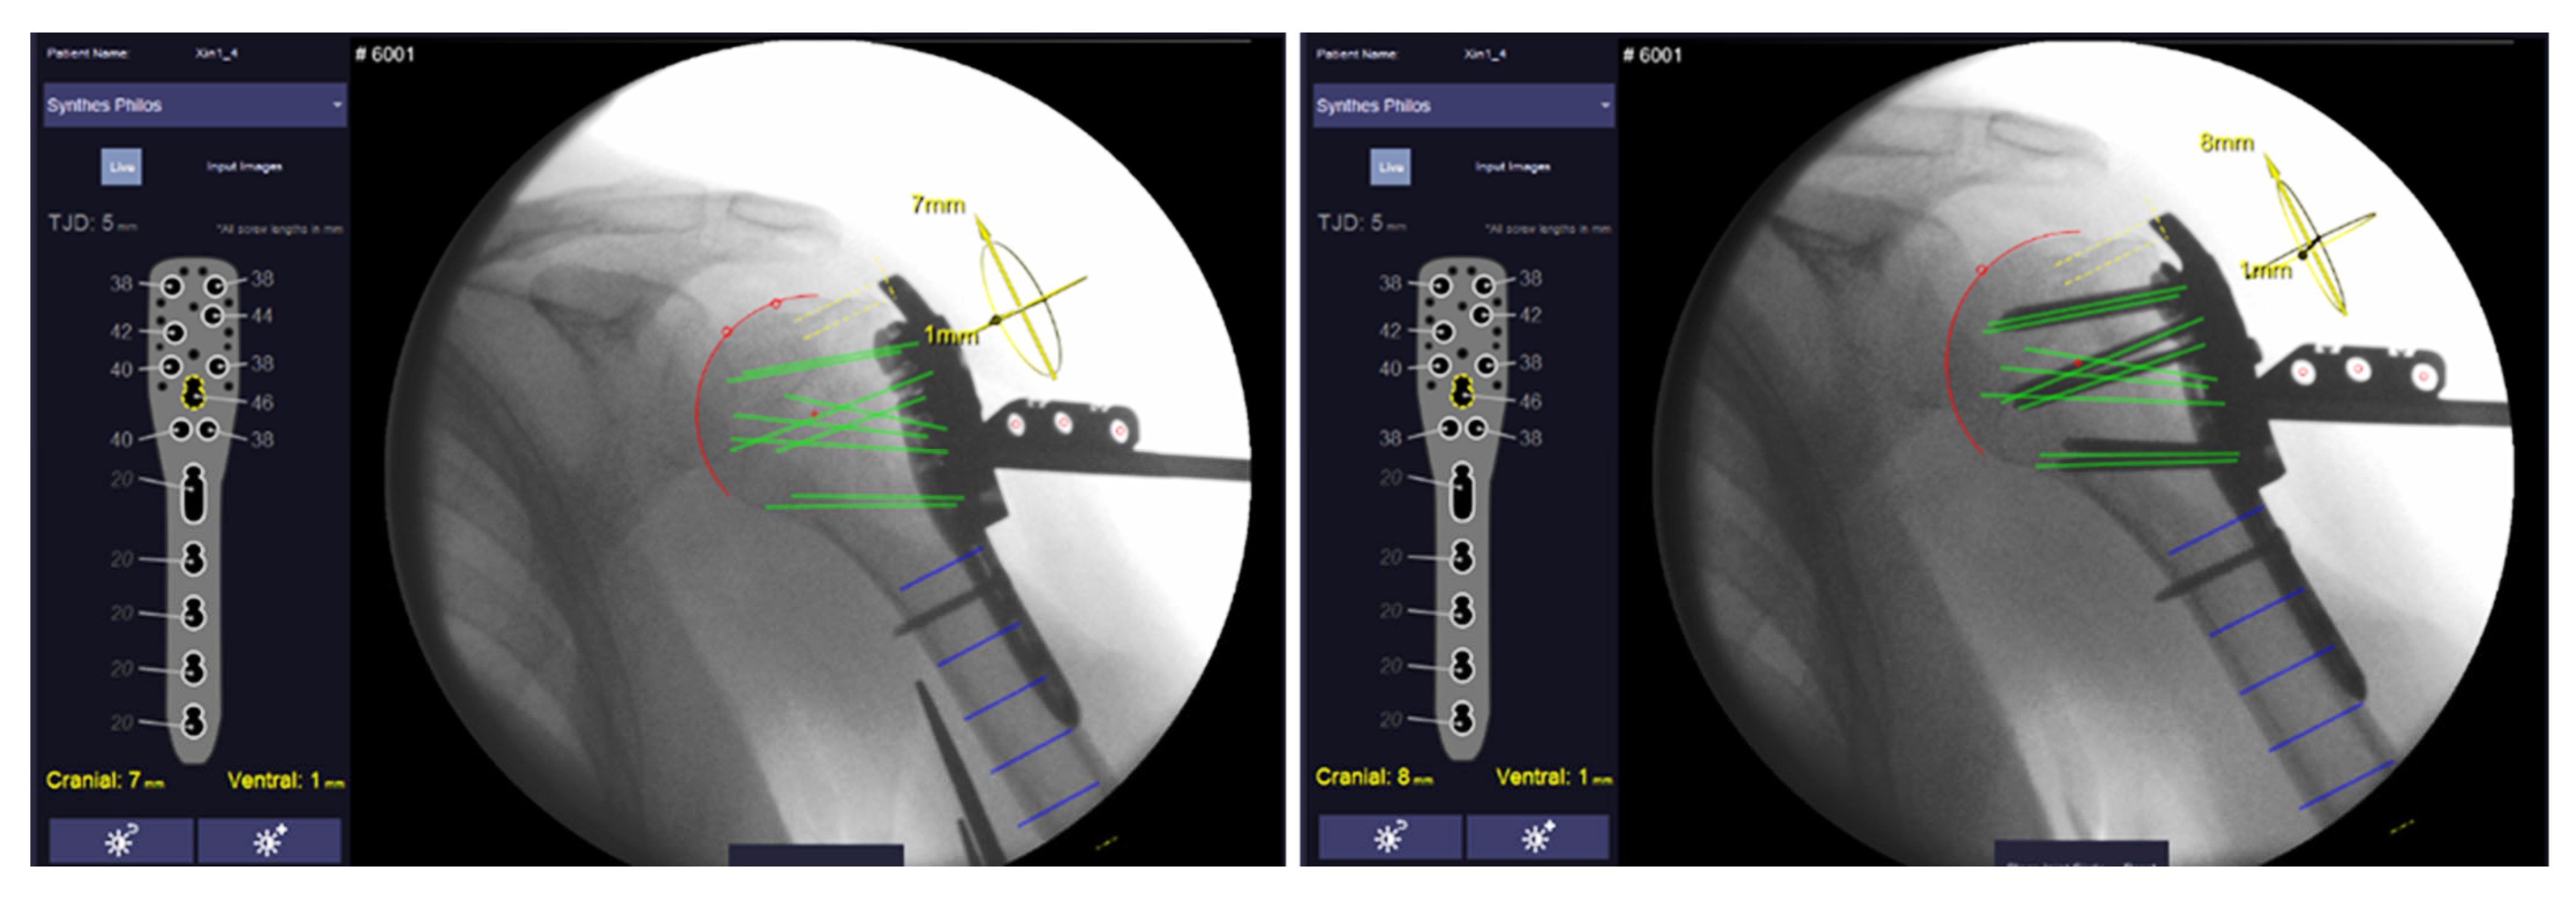

For proximal humeral plating, a stainless-steel marker comprising three cylindrical holes arranged in a defined pattern and two polymer clamps is clipped on a drill sleeve which is attached to a conventional anatomic locking plate (PHILOS ref: 441.901, DePuy Synthes Inc., Raynham, MA, USA) (Figure 1). The nose of the clip locks into the PHILOS guide block to constrain clip rotation. Two anteroposterior X-ray images of the proximal Humerus (including the marker clip) are taken at an angle to determine the position of the humeral head in space in relation to the implant. The boundaries of the humeral head are identified in both images via semi-automatic segmentation. Hereby, the head is estimated as a perfect sphere and best-fit solution candidates are suggested to the operator for final selection. The software calculates screw trajectories based on the marker position and known implant geometry for both X-ray images. By calculating intersection points of the screw trajectories and sphere, proximal screws are virtually truncated to a given tip–joint distance (TJD). Suggested screw lengths (rounded to commercially available increments) are displayed on the software’s graphical user interface (Figure 2).

Figure 2. User interface of the Xin1 software for proximal humeral plating showing the semi-automatically selected humeral head (red circle) and the resulting virtual screw trajectories (green lines). All screw lengths are shown on the left side of the graphical user interface. Left image shows screw length determination after plate prepositioning and right after final screw insertion. Graphical user interface by MeVis BrestCare GmbH.

For the Xin1 procedure, a marker clip was additionally attached to the drill sleeve (Figure 1). After prepositioning the plate, a first pair of X-ray images was taken at an angle of ~30° in an approximately anteroposterior direction. A tablet computer with Xin1 software was connected to the C-arm via PACS (Picture Archiving and Communication System). Image pairs were transferred to the tablet computer on request of the operator during the procedure. The humeral head was segmented by the operator in both images of a pair on the touch screen via the semi-automatic segmentation approach. All proximal screw lengths to a target TJD of 5 mm were calculated using the system from the image pair and outputted on the screen. Eight proximal screws were placed according to the system suggestion using the screw insertion guide. After screw insertion, another image pair was taken for verification of the implant and screw positions.

Image pairs from both stages were formed from the available X-rays and processed with the Xin1 software. An image pair was found valid if the view angle between the images exceeded 15°. So that several valid pairs could be formed, the pair with the largest view angle was selected. Screw lengths and plate positions were computed from the selected pairs for both stages. The plate position is calculated in relation to the anatomy, defined as the offset of the calculated center of the humeral head from the central screw trajectory (screw 7, D-Level) in cranial–caudal and dorsal–ventral directions (Figure 3).